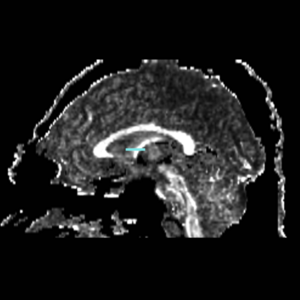

ROI 1) A coronal plane in the most anterior point of the corpus callosum was selected using the mid-saggital plane (Fig.18), and the left and right ROI1s were drawn on the superior side of the corpus callosum (Fig.15)

ROI 2) & ROI 3) The first coronal slice where the left and right corpus connect was selected: the left and right ROI2s were drawn on the superior side of the corpus and the left and right ROI3s were drawn on the inferior side of the corpus (Fig. 16 & 18)

ROI 4) The first coronal slice showing where the middle cerebellar peduncle was slected, and the left and right ROI4s were drawn(Fig. 17 & 19)

Figure 18. Cingulum Bundle ROI's 1, 2, and 3

Figure 19. Cingulum Bundle ROI 4

The color coding of the resulting ROIs is as follows:

ROI 1: Left(7) - Right(8)

ROI 2: Left(9) - Right(16)

ROI 3: Left(11) - Right(12)

ROI 4: Left(13) - Right(14)